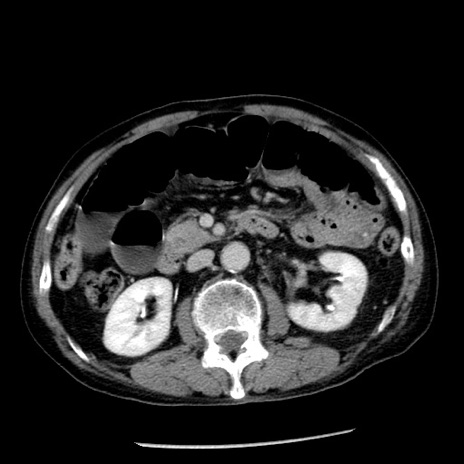

症例26(横断像)

【症例】80歳代男性

【主訴】嘔吐

【現病歴】昨晩2回嘔吐あり、今朝になっても嘔吐あり。来院。

【既往歴】胃潰瘍

【身体所見】意識清明、BT 37.6℃、BP 166/95mmHg、HR 100bpm、SpO2 97%、腹部:平坦・軟、腸蠕動音聴取良好、圧痛なし。

【データ】WBC 21900、CRP 1.46